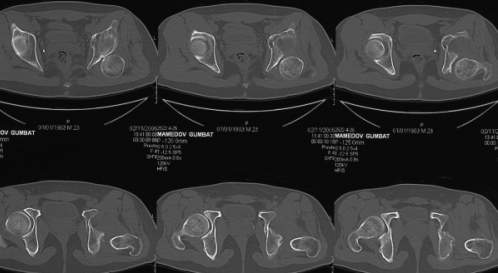

важаемые коллеги,пациент 23 лет (вес 75 кг), обратился к нам по поводу боли в тазобедренном суставе при ходьбе, нестабильность в нем при нагрузке. Ходит с тростью. 8 мес. назад попал в ДТП (никаких медицинских документов у него нет). Стоит ли открываться и вправлять вывих или сразу делать бесцементное тотальное эндопротезирование? С уважением, А. В. Вакуленко Клиника эндопротезирования суставов, г. ДонецкDear All, male patient 23 y.o., body weight 75 kg. Had RTA 8 months ago (medical records unavailable). Now has pain on motion in his left hip. On weight-bearing hip is unstable (patient use cane while walking). Keeping in mind his age, is it worth to perform open reduction? Or just do uncemented THR? Any comments are very welcome.

Здравствуйте. Позвольте поучаствовать в обсуждении. Поскольку пациент в течение 8 месяцев не получил адекватного лечения (видимо и по своей вине тоже), а также учитывая удовлетворительное состояние головки бедра(по данным КТ), есть смысл выполнить открытое вправление головки бедра с возможной фиксацией фрагмента заднего края пластиной. Далее начать восстановление функции сустава, дозированную нагрузку. Возможно молодой возраст пациента поможет ему отдалить время эндопротезирования. Желаю успехов.